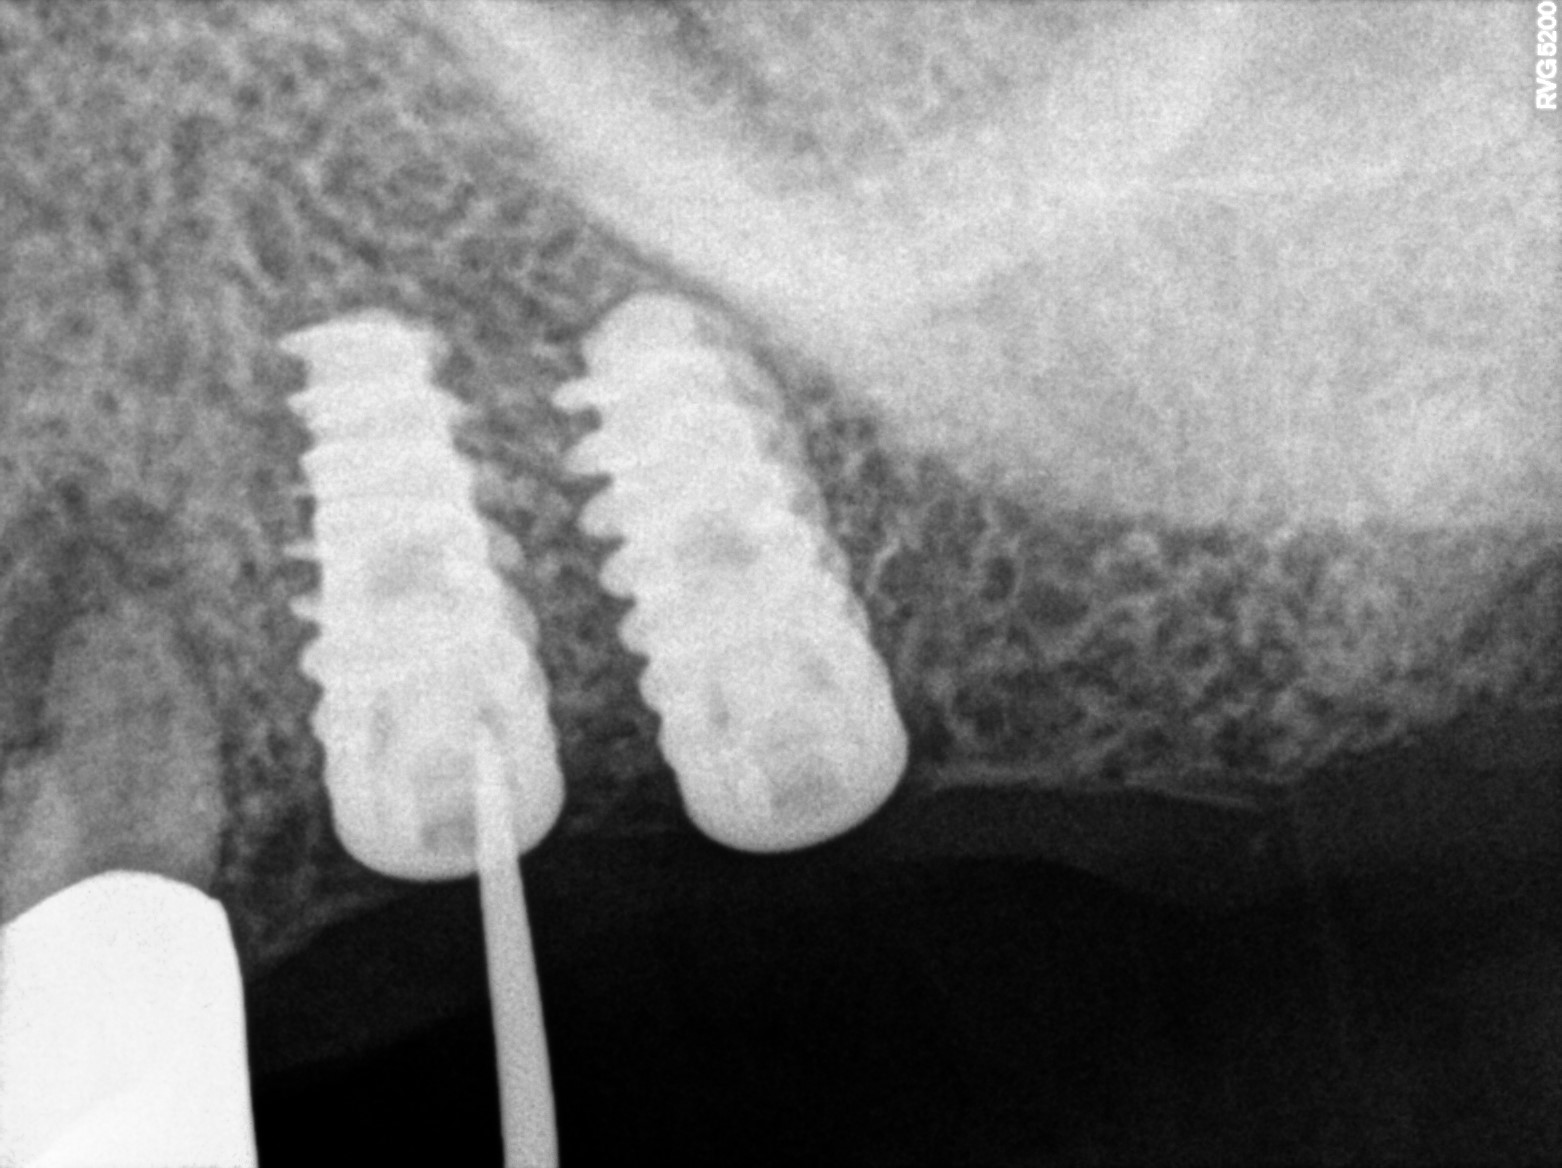

Dental Radiographs FHIR: DocumentReference · LOINC 24641-7

R66.jpg

24641-7

R55.jpg